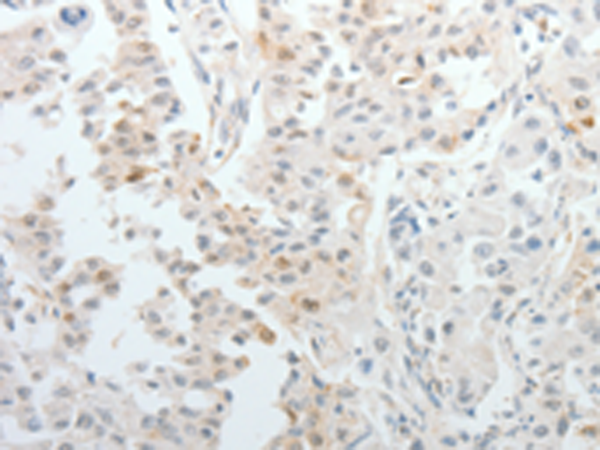

分类: 科研抗体货号: P11097别名: PRMT4应用: IHC反应种属: Human, Mouse, Rat